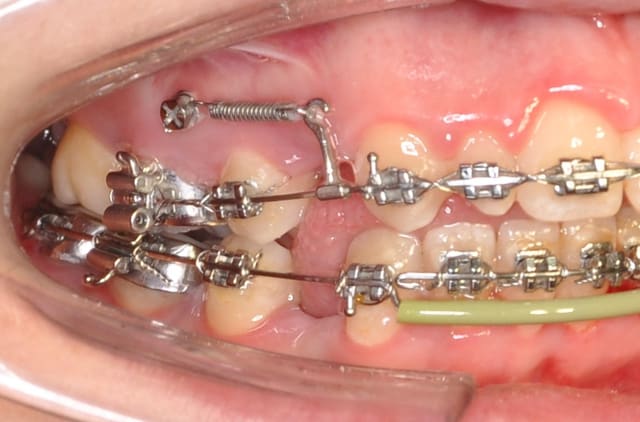

Je voulais que tu me dises ton avis sur cette mécanique

Dsc 0003 ccadd6 - Eugenol

Dsc 0007 rqtmo9 - Eugenol

Dsc 0004 b9m7js - Eugenol

Dsc 0005 s7pxry - Eugenol

Dsc 0006 piv60m - Eugenol

> Je voulais que tu me dises ton avis sur cette mécanique

C'est une construction très élaborée et réfléchie. As-tu la suite ?